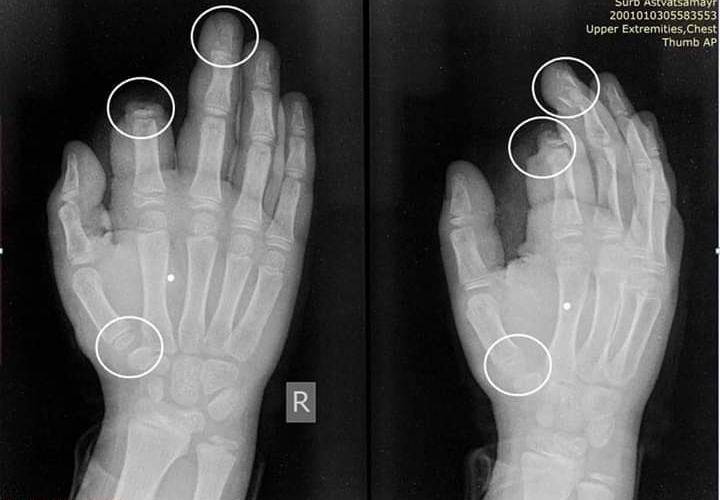

Հ.Գ. նկարում 10 ամյա երեխայի երկու մատի դիստալ ֆալանգների ջնջխման ռենտգեն նկարն է, որը տեղի է ունեցել ամանորյա գիշերը։

49 դեպքում տուժածները ստացել են դաստակի և նախադաստակի տարբեր տեսակի վնասվածքներ։